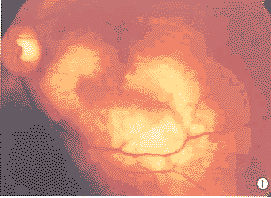

患者郭××,男,23岁,以左眼视力突然下降半年为主诉就诊。病初自认为近视,服药治疗无效,逐渐加重。就诊前半年浴后视力突然降低,眼前大片黑影遮挡,曾在外院诊断为眼底出血,Coat’s病,“中渗”等,用药后视力仍无改善。无外伤、炎症、手术等病史。全身检查未见异常。眼部检查:左眼视力0.1,加镜视力无提高,右眼1.0,屈光间质清,眼底(图1)视盘颞侧血管弓下及黄斑区一地图样黄白色病灶,轻度隆起,高度不一,约2~4 D,范围4 PD×5 PD,边界清晰,其中央一条带状出血,位于视网膜血管下,黄白色病灶周围色暗,病灶向颞下延伸,犹如伪足状达赤道部附近。

FFA(图2,3):动脉期即可见染料渗漏,过程中渗漏增强,后期呈强荧光,形态大小无明显变化,病灶区内有一条状荧光遮蔽带。ICGA:病灶早期呈低荧光,继而低荧光区内出现散在斑点状荧光且随造影时间延长,斑点荧光逐渐增强,后期整个病灶荧光融合,病灶内荧光遮蔽条带渐变模糊。

图1 脉络膜骨瘤眼底彩照 图2,3 脉络骨瘤FFA 图4 脉络膜骨瘤声像图 图5 脉络膜骨瘤CT扫描